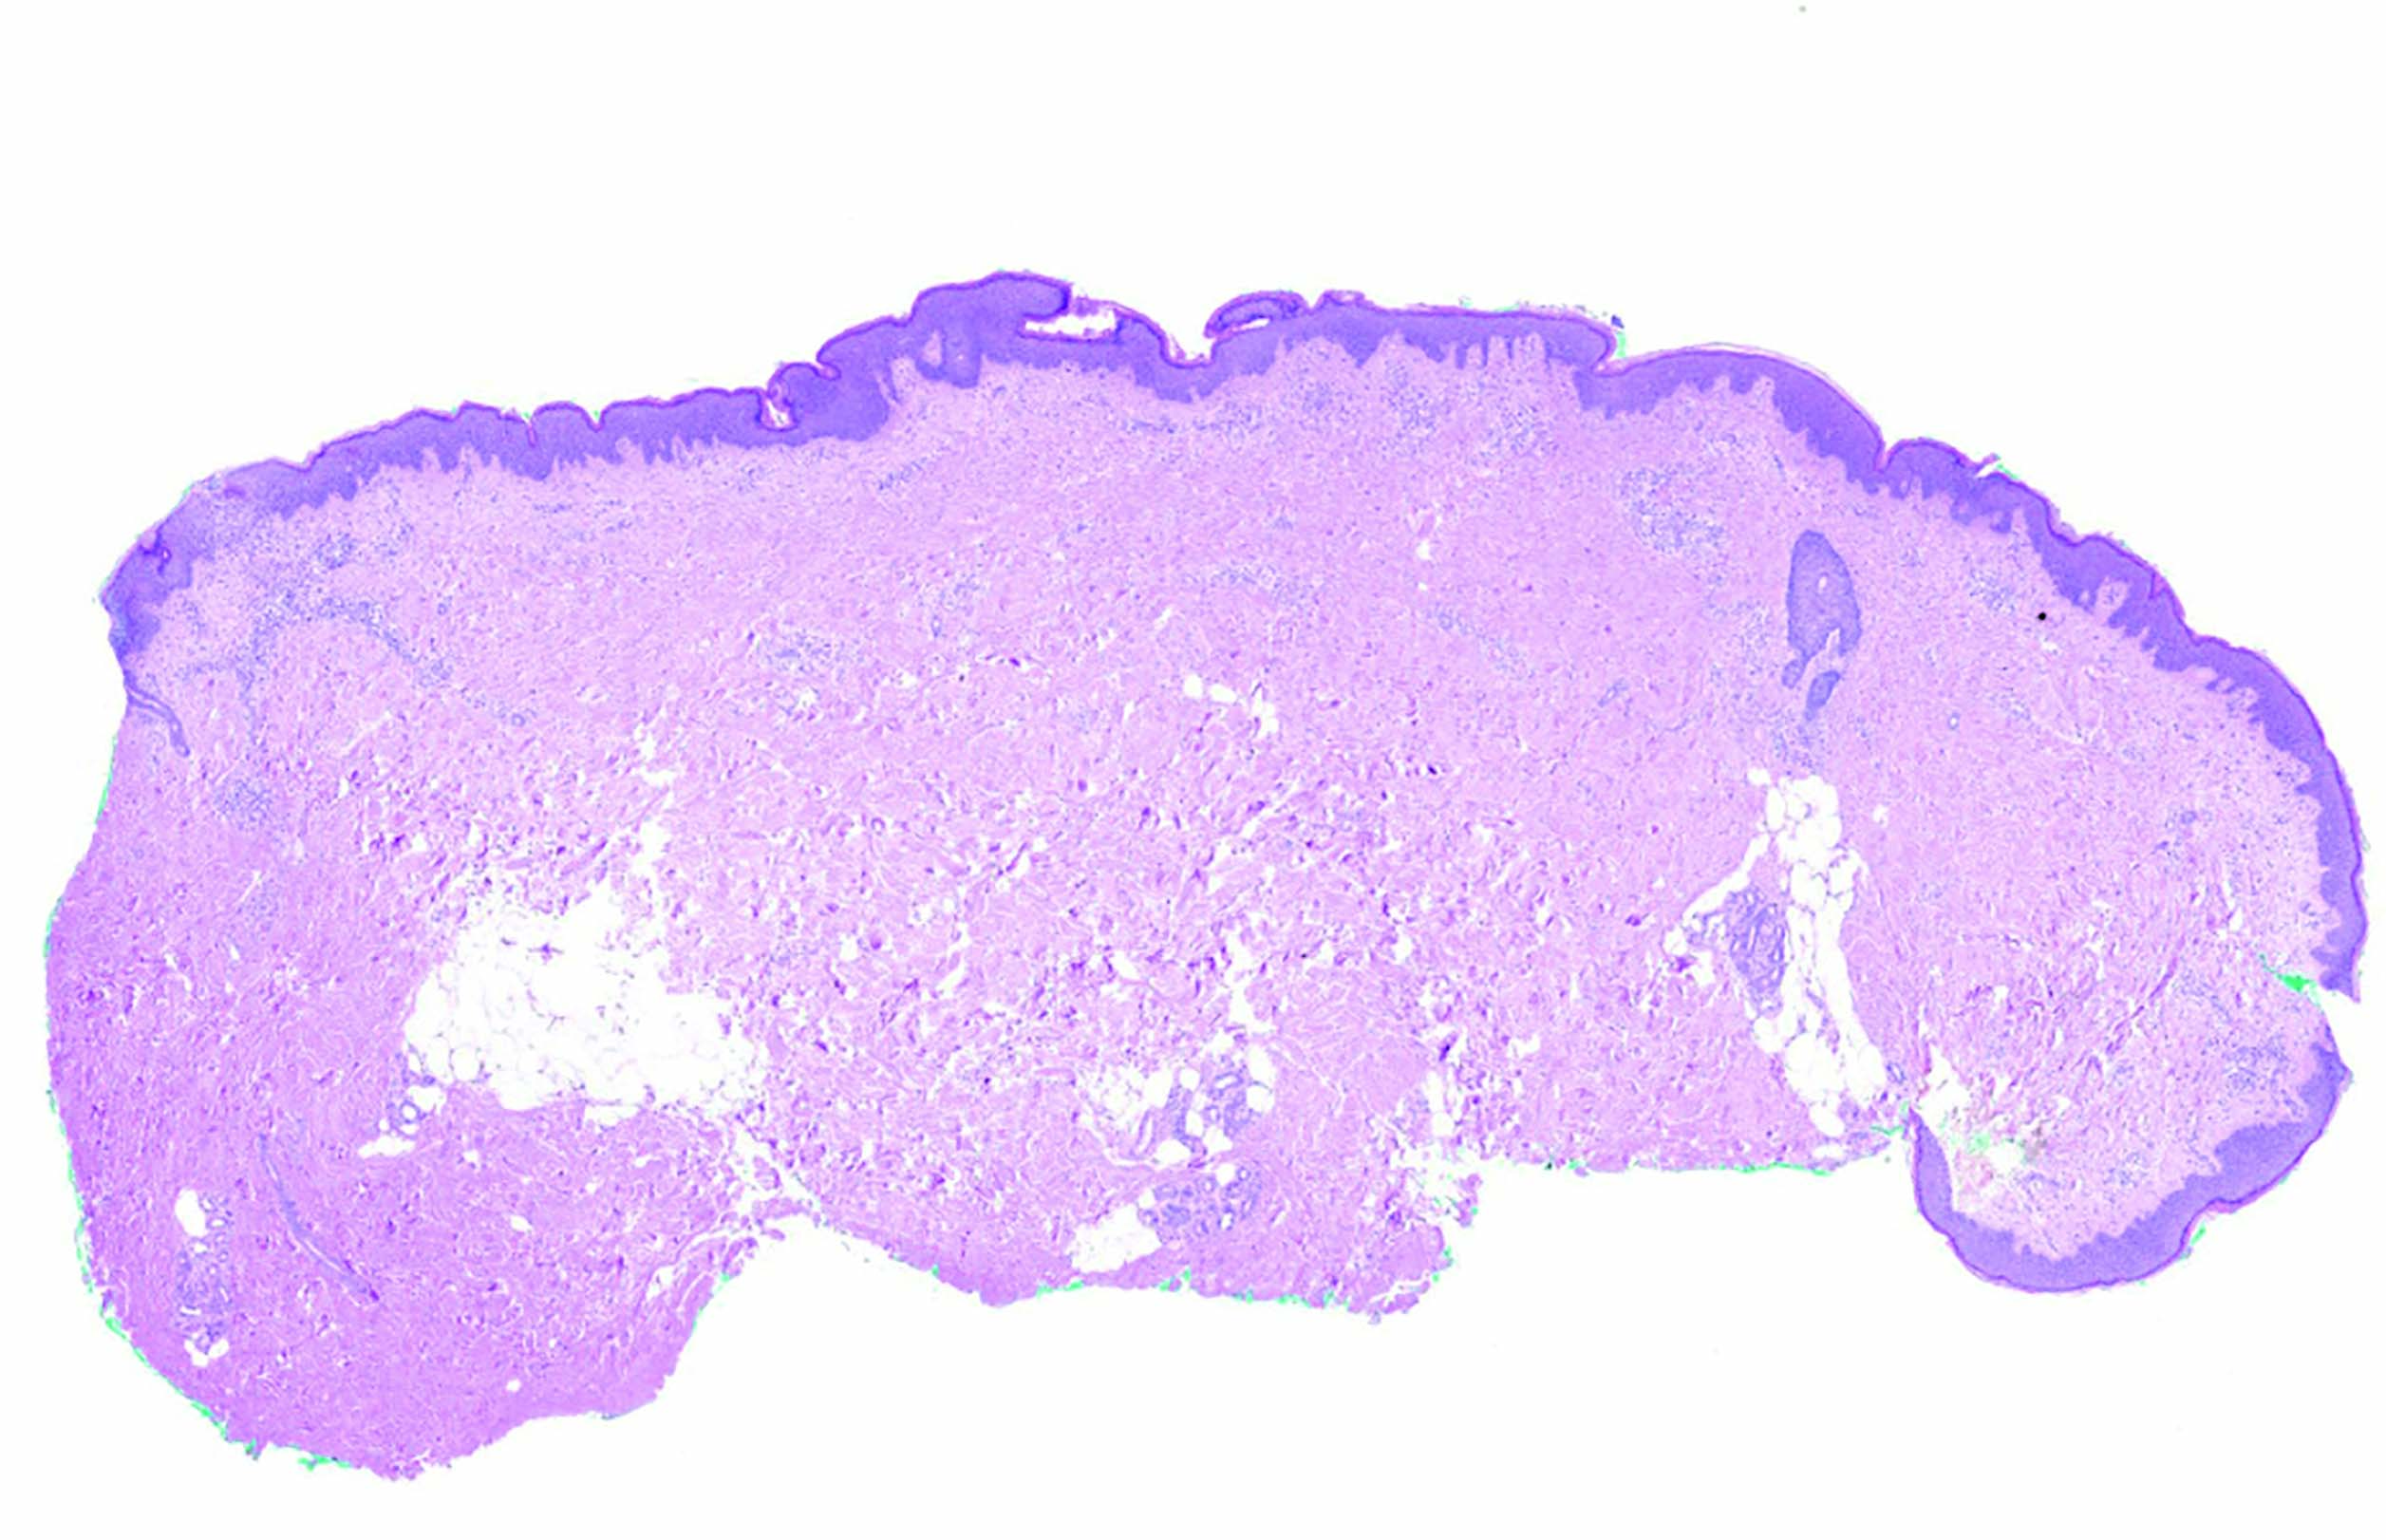

Рис. 2. Неравномерный ортокератоз и акантоз эпидермиса, окраска гематоксилином и эозином (ув. х30)

Fig. 2. Irregular epidermal orthokeratosis and acantosis , staining by hematoxilyn and eosin, x30

Для дифференциальной диагностики гистиоцитоза из клеток Лангерганса с другими гистиоцитарными опухолями было проведено повторное гистологическое и иммуногистохимическое исследование участка пораженной кожи. Гистологическое исследование показало, что в исследованных образцах кожи слабо выражен неравномерный ортокератоз и акантоз эпидермиса (рис. 2). В верхних слоях сетчатого слоя дермы обнаруживаются периваскулярные инфильтраты, образованные клетками среднего размера с овальными ядрами, 1–2 мелкими ядрышками в них и амфофильной цитоплазмой. В некоторых таких клетках можно различить складку ядерной мембраны (дендритные клетки). Среди них рассеяны немногочисленные лимфоциты, гистиоциты и малочисленные эозинофильные гранулоциты (рис. 3, 4).